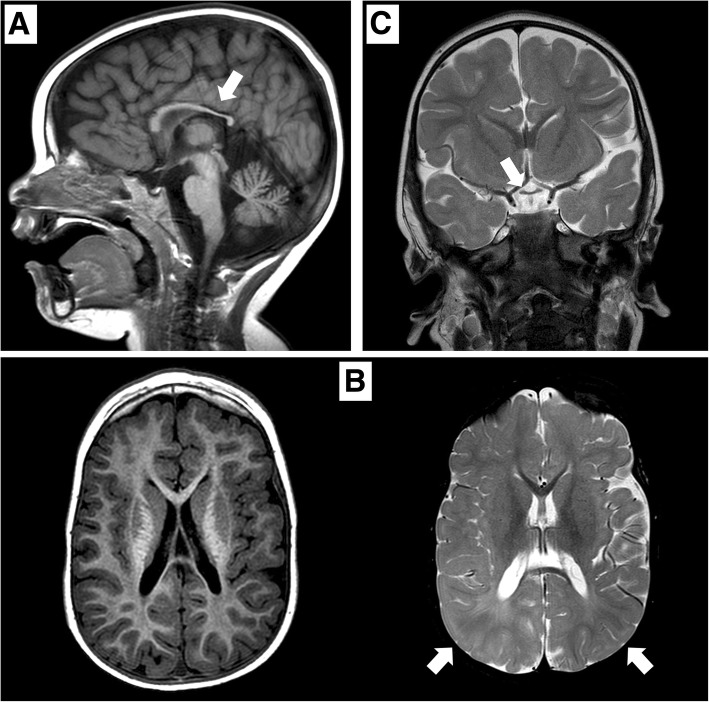

根据《人的基因序列变化与人体疾病表征》,过去有部分机构和医务人员认为德莫塞尔综合征不是遗传性疾病,甚至有人认为该病不是由基因引起的,德莫塞尔综合征发生的内在基因原因被忽视。佳学基因通过基因解码找到并定位了导致这一疾病发生的原因,提出了德莫塞尔综合征的遗传风险,并建议通过基因检测明确和排除风险,让后代、二胎不再患有德莫塞尔综合征,实现德莫塞尔综合征遗传阻断的目的。佳学基因病案集中一个患者是一名 2015 年出生的男孩,是健康父母的第二个孩子。 他有一个健康的姐姐,姐姐于 2011 年出生。他出生时妊娠 376/7 周,顺产(体重,2.4kg;z-分数,->1,65;长度,45-cm;z-分数, − 2.45;头围,31 cm;z 分数,- 1.84;Apgar 评分,1 分钟 8 分和 5〉 分钟 8 分)。 出生后 5 小时,他因低血糖(床旁检查,29mg/dl)被送入新生儿病房,并接受了 72 小时的静脉葡萄糖输注。 先天性巨细胞病毒感染的脑超声和实验室检查结果均正常。6个月大时的初步评估显示整体发育迟缓。 患者的体格、营养和身高对于他的年龄而言是正常的(z 评分,+ 0.64)。 检查显示小头畸形(z 评分,− 1.56)、畸形特征(薄上唇、尖腭、低植发、长人中、广泛的睑裂)、肢体异常(右脚趾和双脚足底垫植入异常) )、小阴茎和隐睾。患者出现全身性肌张力减退; 他无法实现头部控制,并表现出水平眼球震颤、眼球运动障碍和视力障碍。 没有癫痫发作史。 头颅磁共振成像 (MRI) 显示髓鞘形成延迟、胼胝体发育不全(图 1)和垂体发育不全。 没有闪光视觉诱发电位反应。

矢状位 T1 加权图像显示胼胝体发育不全(白色箭头)。 b 轴向 T1 加权(左)和轴向 T2 加权(右)图像显示胼胝体发育不全和双侧皮层下顶叶白质(白色箭头)中改变的、不明确的信号。 c 显示视交叉发育不全的冠状 T2 加权图像(白色箭头)

在 2 岁时,患者无法保持目光接触,也没有发展语言技能。 直到 3 岁时,他才能独立坐下。此时,头颅 MRI 显示双侧视神经发育不全,并证实胼胝体发育不全(图 (图 1).1)。 为评估先天性心脏缺陷而进行的超声心动图显示无阻塞的室间隔肥大。